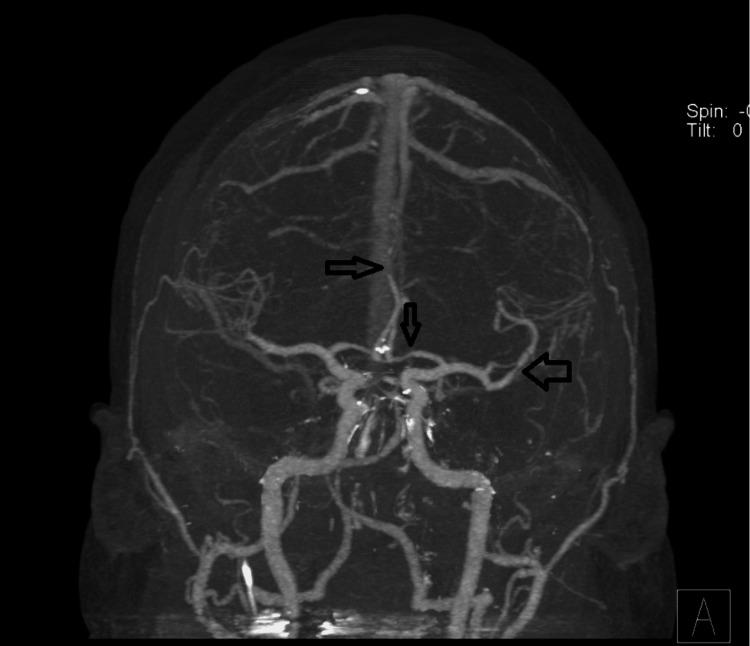

Reversible cerebral vasoconstriction syndrome (RCVS) is not an uncommon condition. It should be suspected in young patients with new onset headaches and neurologic deficits. We report a 38-year-old male patient with a history of depression on desvenlafaxine for two years and no other triggering factor who was diagnosed with RCVS confirmed by cerebral angiogram. Discontinuation of the medication and calcium channel blockers initiation led to rapid clinical improvement. The diagnosis was further confirmed by angiographic improvement two months later. Although the association of selective serotonin reuptake inhibitors (SSRI)/ serotonin norepinephrine reuptake inhibitors (SNRI) with RCVS has been reported frequently, desvenlafaxine is a much less reported trigger, with only nine cases in total. In contrast to prior reported cases where the time from exposure to onset of RCVS was weeks to months, the time interval, in this case, was two years. This case report aims to support previous literature in suggestion of this association.

可逆性脑血管收缩综合征(RCVS)并非罕见疾病。对于新发头痛和神经功能缺损的年轻患者,应怀疑患有此病。我们报告一例38岁男性患者,有两年服用去甲文拉法辛治疗抑郁症的病史,无其他诱发因素,经脑血管造影确诊为RCVS。停用该药物并开始使用钙通道阻滞剂后,临床症状迅速改善。两个月后的血管造影改善进一步证实了诊断。尽管选择性5-羟色胺再摄取抑制剂(SSRI)/5-羟色胺去甲肾上腺素再摄取抑制剂(SNRI)与RCVS的关联已被频繁报道,但去甲文拉法辛作为诱发因素的报道要少得多,总共仅有9例。与之前报道的病例中从接触药物到RCVS发病的时间为数周至数月不同,本病例的时间间隔为两年。本病例报告旨在支持先前文献中关于这种关联的提示。